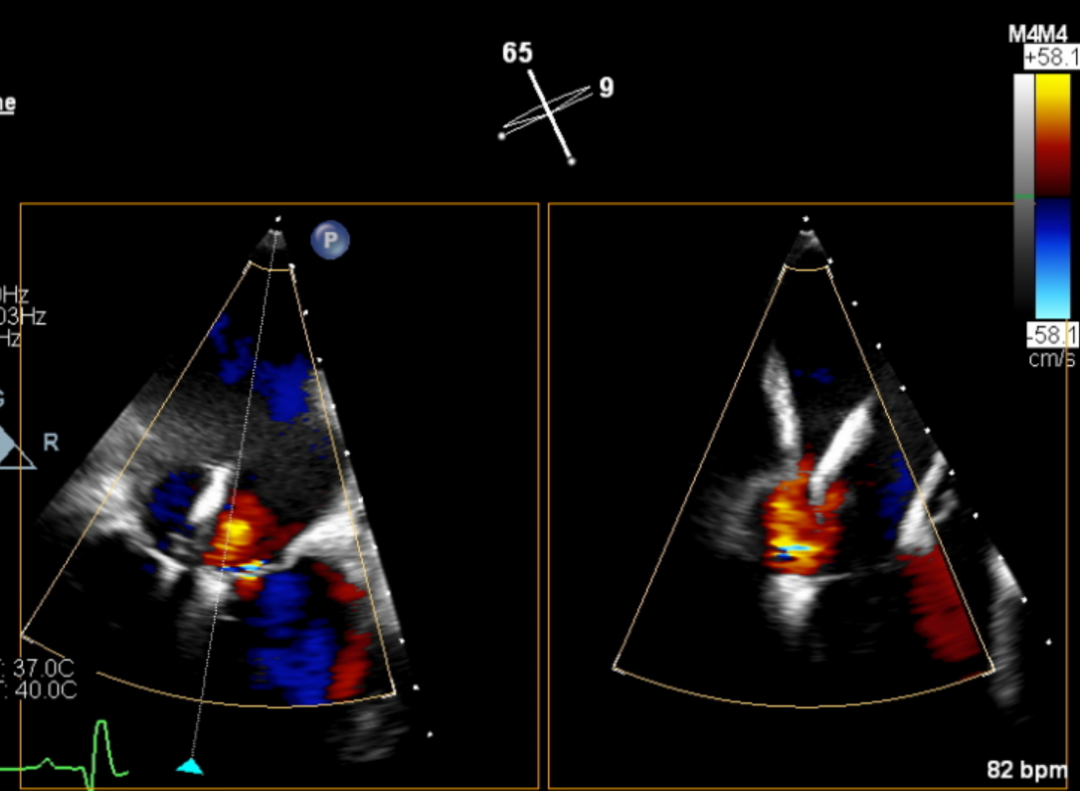

图片

第一枚瓣膜夹夹合后二尖瓣仍有较多返流